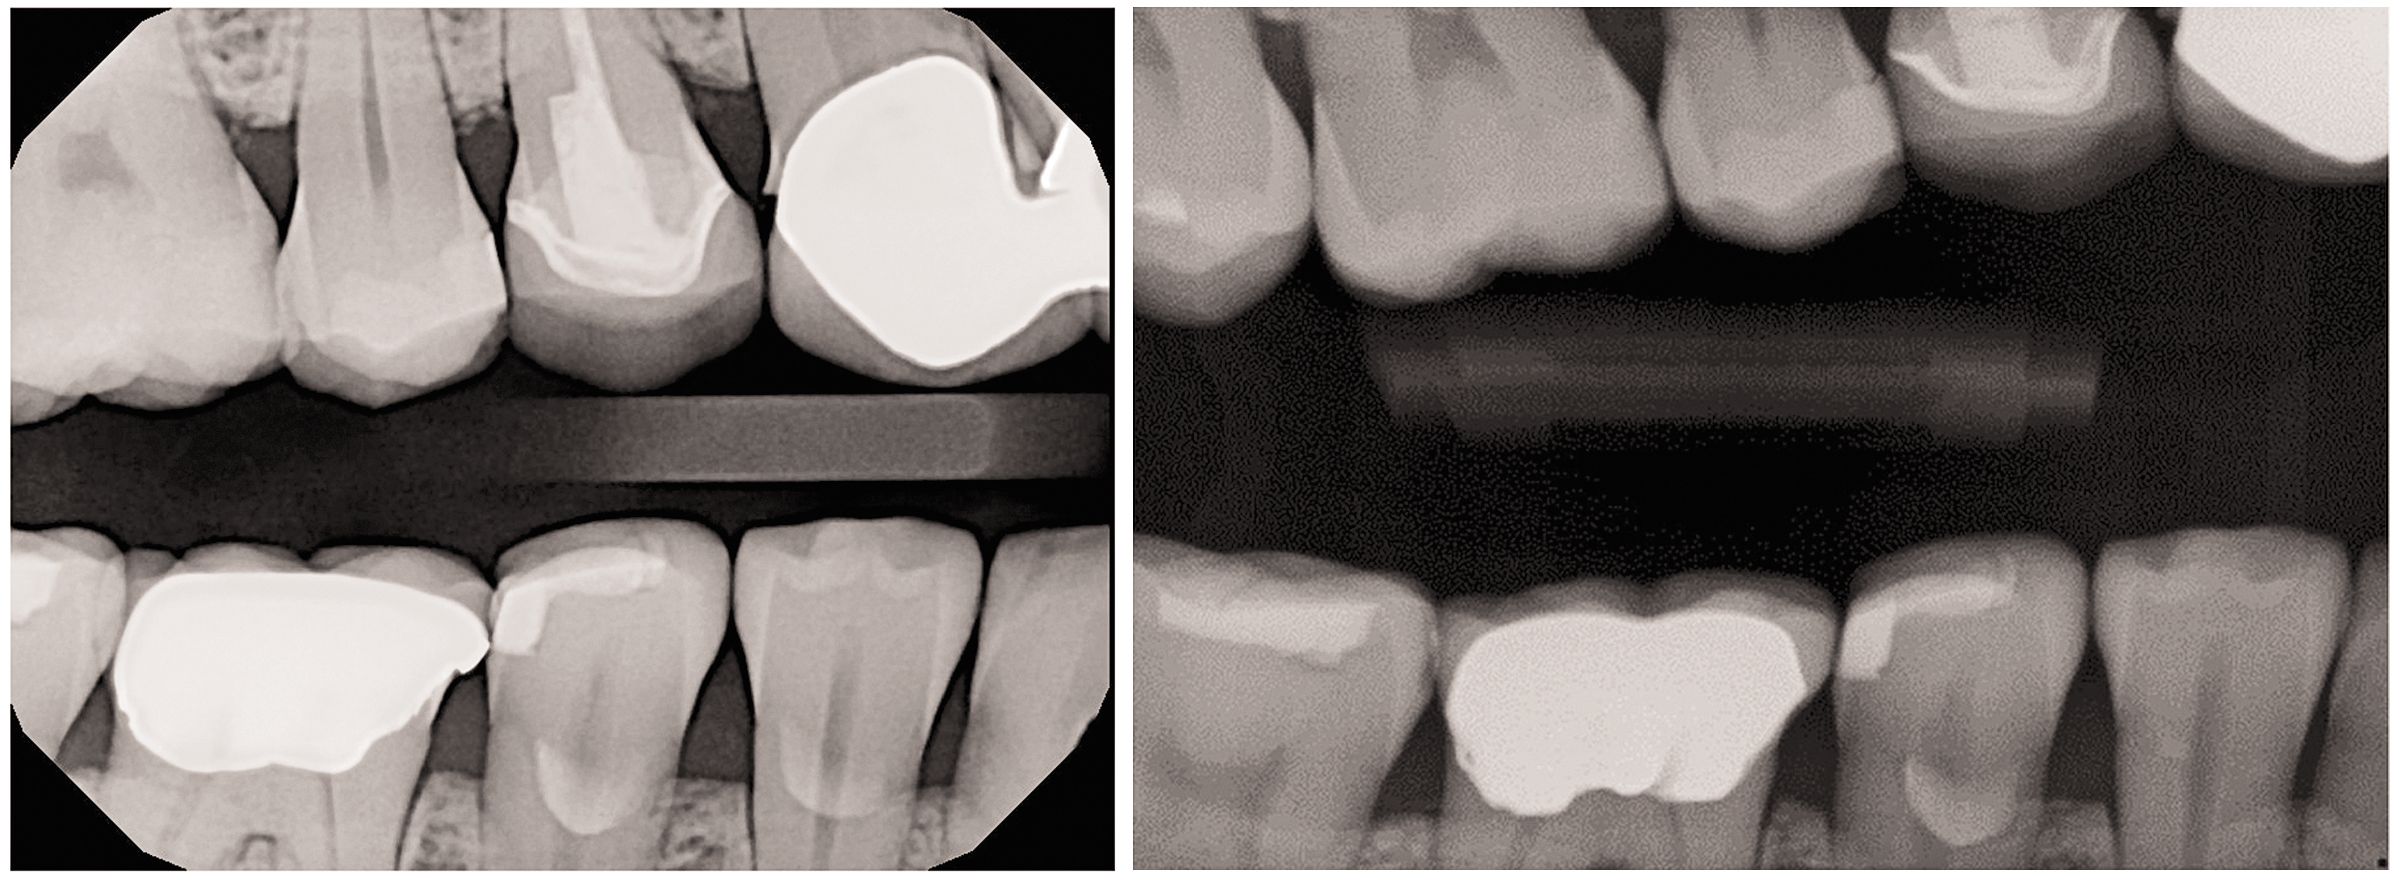

When using DEXIS Platinum sensors during the study*, patients found it easier to close completely on the DEXIS biteblocks including bitewing (seen here) and in periapical positions.

How DEXIS image quality compares to competitive sensors at different exposure times.

In a laboratory setting*, image quality was recently analyzed with respect to dose. The results were that the image quality obtained using the DEXIS Platinum sensor demonstrated more consistency across both low and high radiation dose, when compared with other competitive sensors. In addition, the DEXIS Platinum sensor provided higher diagnostic image quality results at lower radiation doses when compared to these competitive sensors.

Post-capture, images can be displayed at ultra-large sizes and even enlarged without pixilation or loss of quality. In addition to the notable image quality of initially captured images obtained using the DEXIS Platinum sensor, DEXIS imaging software has another effective tool, ClearVu™. Apply this acclaimed image enhancement tool that utilizes advanced algorithms to provide further definition, detail, and depth for acquired images.